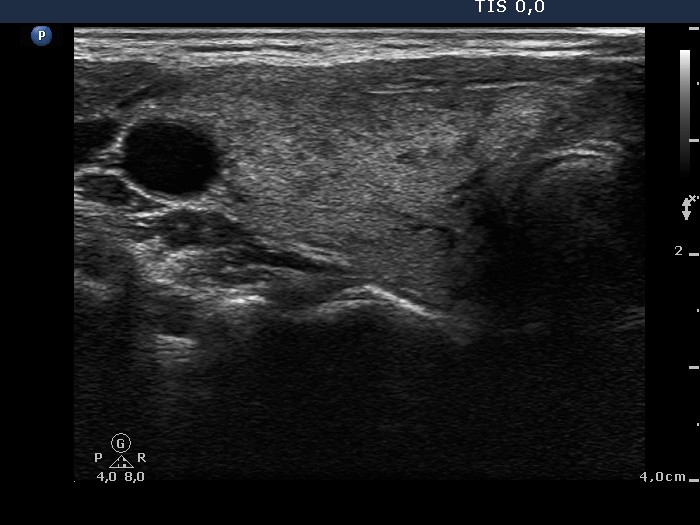

Graves' disease - Case 15.

Follow-up investigation 36 months after first visit (ultrasonographic picture 1)

Patient on daily 10 mg methimazole therapy in euthyroid state

Right lobe, horizontal scan. Only small moderately hypoechogenic areas are found.